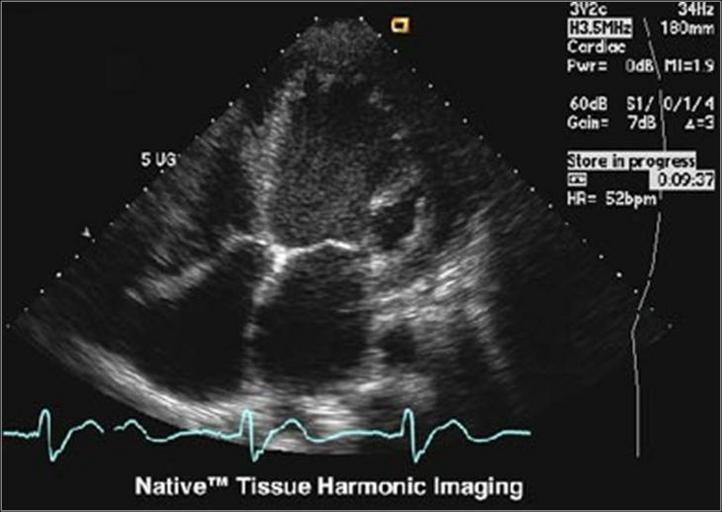

| View Original: | Heart with THI.jpg (730x518) | |||

| Keywords: Heart with THI.jpg ultrasound heart tissue harmonic imaging 4-chamber-view 2006-08-30 own assumed Schomynv Check categories 2009 February 11 de wikipedia Tissue_Harmonic_Imaging 2 Medical ultrasound | ||||